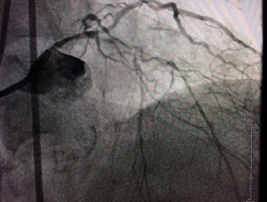

旋磨术手术中

入院后两周,袁小蓉带领冠脉介入团队经过精心准备后,对陈大爷施行了最先进的冠脉血管内超声检查术+冠脉内膜斑块旋磨术。

术前,介入专家首先对陈大爷进行了冠脉血管内超声检查,明确血管内结构以及钙化病变位置和严重程度。然后将带有钻石颗粒的高速旋磨头送入患者血管内的钙化部位,在医生的精细操作下,位于血管内的磨头便以每分钟10多万次的转速开始高速旋转,根据“差异性切割”(即只针对严重钙化和纤维化的病变斑块组织而不损伤正常组织)原理,将阻塞血管的动脉斑块迅速磨成极其微小的颗粒,随血液循环至血管远端并通过毛细血管床吸收。经过几次旋磨后,阻塞血管腔的钙化斑块被逐渐消除,在进行球囊扩张之后,在两支血管内顺利植入四枚支架,成功开通血管,手术时间总共用时1个多小时。